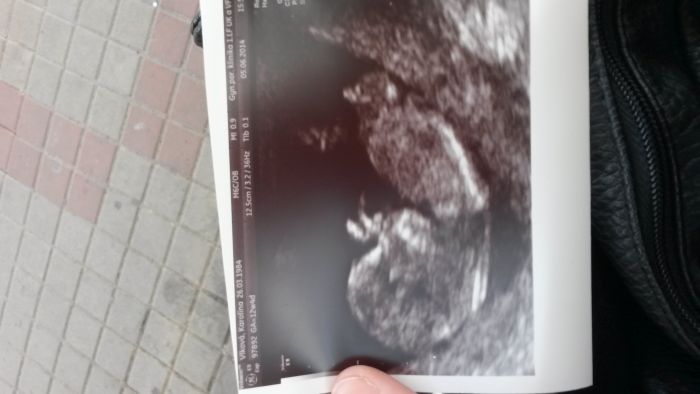

Tak holky vsechno naprosto v poradku :) ma 6cm a termin zustal 14.12. ;) na pohlavi,kdyz jsem se ptala,tak rikala,ze se ani nebude koukat,ze je jeste brzo ;) jinak delala mi ho pres bricho cca 20min,merila hlavicku,zkoumala pupecnik,moje cevy atd,jestli ma prcem dve ruce,dve nohy ;) tlukot srdce a nevim,co vsechnk. Kazdopadne prcek jednu ruku za hlavou a nohu pres nohu,pohoda nejvetsi :D

[558307] jop,mam pocit,ze mame stejne i prvni den posl.ms - 9.3. A abych to upresnila merilo mimco 58mm ;)

Akorat nevim proc se mi ta fotka pretocila,ma bejt norm.na sirku,ale to je fuk :)